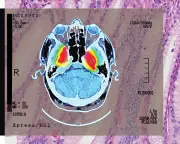

The MHRA is investigating UK peptide clinics for potentially unlawful claims about unregulated therapies, as a Guardian investigation reveals widespread promotion of experimental treatments with little scientific evidence.